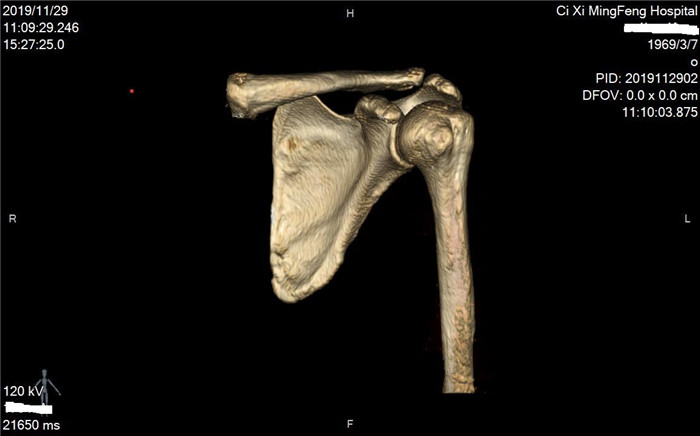

明峰CT搭載了領(lǐng)先的硬件技術(shù)平臺及系統(tǒng),強(qiáng)大的掃描能力可滿足臨床的各種要求,呈現(xiàn)更極致的細(xì)節(jié),為各臨床科室提供高品質(zhì)的圖像。薄層掃描,消除部分容積效應(yīng),提高各向同性。配合高分辨率算法,有助于細(xì)微結(jié)構(gòu)和形態(tài)學(xué)顯示。